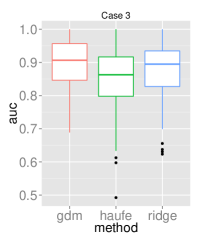

To assess the discriminative performance and reproducibility of the compared methods under varying confounding scenarios, we used the ADNI dataset. We simulated four distinct training scenarios in increasing potential for confounding effects: Case 1: AD + CN subjects, mean age balanced, Case 2: CN + AD, mean age balanced, Case 3: AD + CN, oldest ADs, youngest CNs, Case 4: CN + AD, oldest ADs, youngest CNs.

All models had their respective parameters () cross-validated in an inner fold before performing out-of-sample prediction on a left out test set consisting of equal numbers of AD and CN subjects with balanced mean age. Furthermore, the inner product of training model parameters was compared between folds to assess the reproducibility of models. Training and testing folds were shuffled 100 times to yield a distribution.

The prediction accuracies and the model reproducibility for the above cases are shown in figure 2. The results demonstrate that while GDM is not a purely discriminative model, its predictions outperformed ridge regression in all four cases. Regarding reproducibility, the Haufe et al. (2014) procedure yielded the most stable models since it yields a purely generative model. However, GDM was more reproducible than ridge regression.